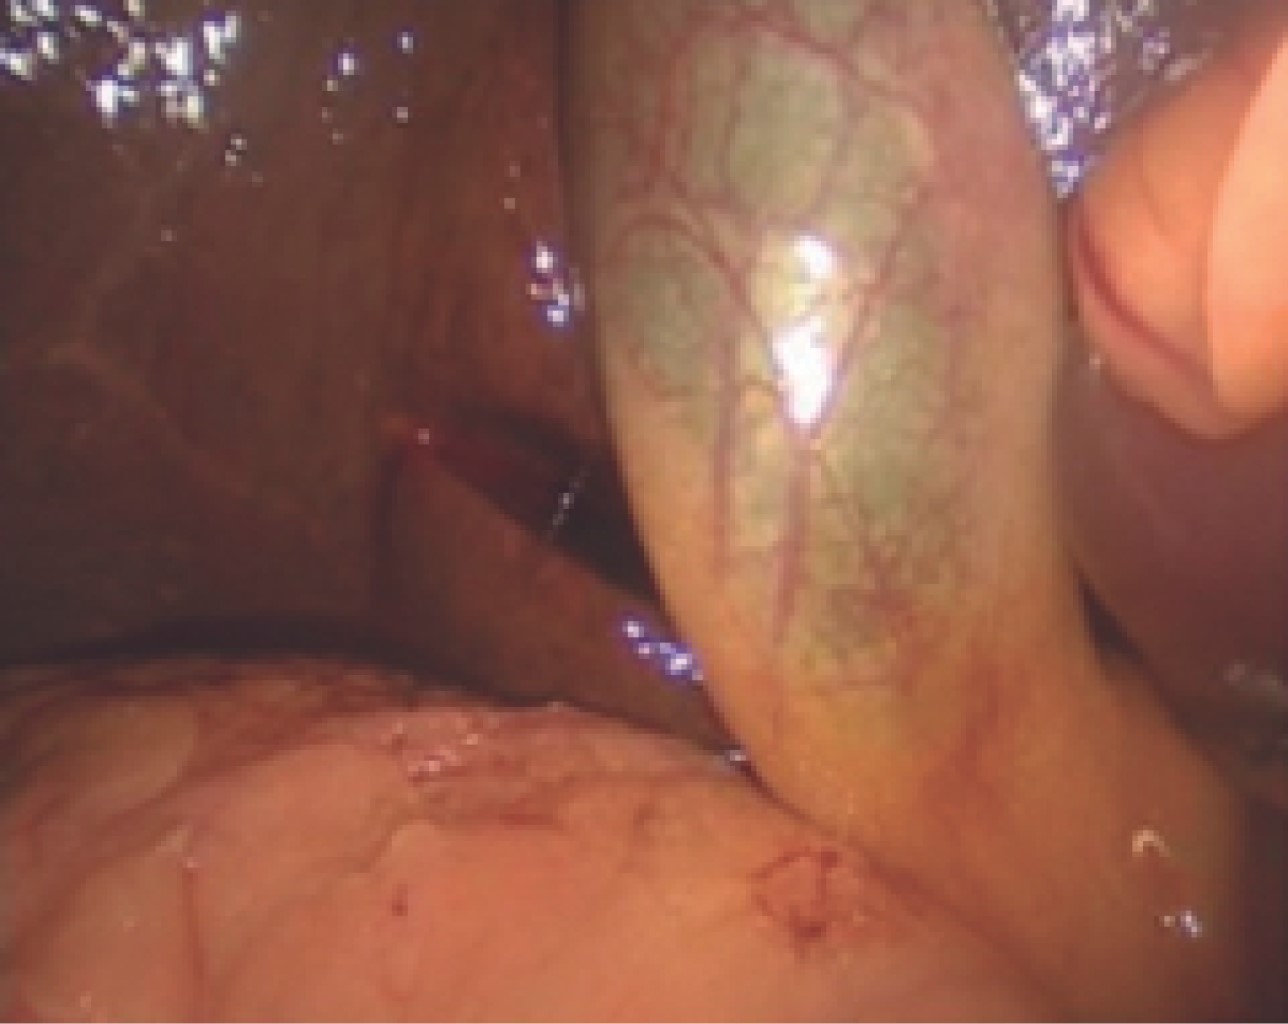

The histopathological diagnoses of the 60 operated patients were compatible with acute chronic cholecystitis and coincided with adhesions of the greater omentum, duodenum, transverse colon to Hartman's pouch, or body, or gallbladder fundus or that the greater omentum completely covered the entire gallbladder as shown in Figures 4, 5 and 6.

Figure 6